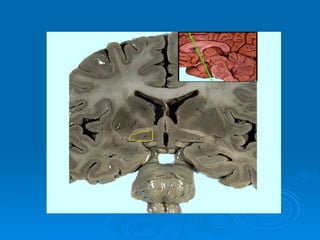

Localização abaixo do tálamo Tamanho de uma colher de chá Importantes funções relacionadas ao controle da atividade visceral ESTRUTURAS Situada nas paredes laterais do III ventrículo ABAIXO DO SULCO HIPOTALÂMICO 1- corpos mamilares = 2 eminências arredondadas de substância cinzenta evidentes na parte anterior da fossa interpeduncular. 2 – quiasma óptico = parte anterior do assoalho ventricular – recebe fibras dos nervos ópticos que aí se cruzam 3 – túber cinério – área ligeiramente cinzenta, mediana, situada atrás do quiasma óptico e na frente dos corpos mamilares – hipófise se prende através do infundíbulo. 4 – infundíbulo = forma de funil que prende a hipófise

NÚCLEOS   Supra-óptico – n.supraquiasmático n. supra-óptico n. paraventricular Tuberal  n. ventromedial n. dorsomedial n. arqueado ou infundibular Mamilar  n. mamilares n. posterior

Localização abaixo dotálamo Tamanho de uma colher de chá Importantes funções relacionadas ao controle da atividade visceral ESTRUTURAS Situada nas paredes laterais do III ventrículo ABAIXO DO SULCO HIPOTALÂMICO 1- corpos mamilares = 2 eminências arredondadas de substância cinzenta evidentes na parte anterior da fossa interpeduncular. 2 – quiasma óptico = parte anterior do assoalho ventricular – recebe fibras dos nervos ópticos que aí se cruzam 3 – túber cinério – área ligeiramente cinzenta, mediana, situada atrás do quiasma óptico e na frente dos corpos mamilares – hipófise se prende através do infundíbulo. 4 – infundíbulo = forma de funil que prende a hipófise